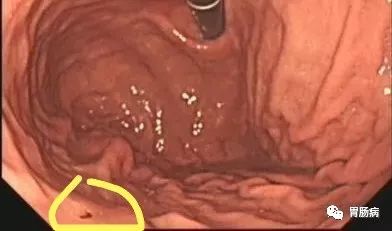

案例二:

王女士,女,53岁,银行职员,因“消化不良”就诊,在医生苦口婆心的劝说下,不情愿地做了胃镜。

早期胃癌胃镜图片

胃镜可以直观的观察胃内病变的形态,病理组织学检查能够观察细胞形态的变化,两者结合对胃癌的确诊率达98%以上。

更重要的是,胃镜结合染色检查能更多的发现早期胃癌。

早期的胃癌不仅能够通过胃镜进发现,甚至可以通过它进行切除。病灶大小于等于2 cm、无合并溃疡的分化型黏膜内癌,胃黏膜高级别上皮内瘤变,可通过胃镜进行切除。